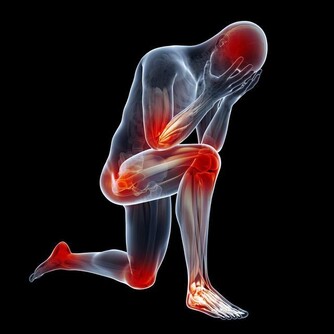

飲用方法: 1.每日約一杯(50毫升),年紀大的人每次20毫升左右; 2.每日飲一至兩次; 3.浸過酒的洋蔥片一起食用更好; 4.不喝酒的人,可用兩倍左右的開水稀釋後飲用或每次倒入電鍋內煮約4至5分鐘,蒸發酒精後飲用。 5.若然喜歡甜的,可加入一點蜂蜜。 紅酒泡洋蔥在日本非常流行!它究竟能治哪些病? 一. 高血壓的患者,飲了之後血壓正常且安定,還能降低糖尿值,降低血糖。 二. 最妙的是對老花眼也有很大的改善,長期飲用後不用戴眼鏡也可以閱讀一般的周刊、雜誌。 三. 每晚都要去幾次廁所的夜晚頻尿症,喝了兩天後,不可思議地恢復正常了。 四. 每天夜裡醒來,一直到天亮都不能再入睡的,或者不吃安眠藥就睡不著的失眠族,飲用後也會逐步緩解失眠症狀。 五. 眼睛疲勞後看東西模糊不清,喝了之後第二天就好多了。 六. 經常肚子會脹,有便秘的人,喝了後第二天便可正常排便。 花錢不多又簡單的方法,功效很顯著,不妨一試哦! 討厭吃洋蔥嗎?看看下面的文章,即使它不那麼可口,為了身體好,也請多多食用! 【洋蔥比骨質酥鬆症的藥有效】 很多人不愛用洋蔥做菜,切的時候會讓人流眼淚,很多人也很討厭洋蔥味。但是想要讓自己骨骼結實、身體長得高、預防骨質酥鬆症的人,最好還是乖乖地捏著鼻子吃洋蔥吧。因為權威期刊「自然」的最新研究報告指出,洋蔥是最能夠防止骨質流失的一種蔬菜。洋蔥預防骨質流失的效果,甚至比骨質酥鬆症治療藥品還要好! 【洋蔥可以預防膽固醇過高】 據哈佛醫學院心臟科教授介紹,每天生吃半個洋蔥,或喝等量的洋蔥汁,平均可增加心臟病人約30%的HDL含量(HDL為高密度脂蛋白膽固醇,一種被認為有助於預防動脈粥狀硬化的膽固醇,也是一種的好的膽固醇)有利於保護心臟。 【洋蔥可以分解脂肪】 克多博士讓診所里的心臟病人每天吃洋蔥,結果發現洋蔥里所含的化合物也能阻止血小板凝結,並加速血液凝塊溶解。所以,當你享用高脂肪食物時,最好能搭配些許洋蔥,將有助於抵銷高脂肪食物引起的血液凝塊。所以說牛排通常搭配洋蔥一起吃,是很有道理的。 【洋蔥可以預防胃癌】 洋蔥和大蒜、大蔥、韭菜這些蔥屬蔬菜,都含有抗癌的化學物質,研究人員在中國山東省一個胃癌罹患率很高的地方所做的調查發現,當洋蔥吃得越多,得胃癌的機率就越低。 【洋蔥可以對抗哮喘】 洋蔥含有至少三種抗發炎的天然化學物質,可以治療哮喘。由於洋蔥可以抑制組織胺的活動,而組織胺正是一種會引起哮喘過敏症狀的化學物質。另外根據德國的研究,洋蔥可以使哮喘的發作機率降低。